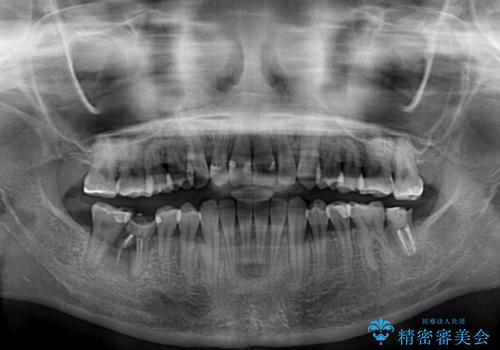

- 上下前歯の開咬とデコボコを気にして来院された患者様です。

開咬(オープンバイト)はインビザラインによる矯正治療がワイヤー装置と比べて圧倒的に有利であるため、インビザラインによる矯正治療を行うこととしました。

通院されなかった時期があって治療期間が長くなったり、奥歯に抜歯が必要な歯があったりと、治療は一筋縄にはいきませんでしたが、何とか治療を終えることができました。

今後はインプラント治療やむし歯治療を進めて行く予定です。